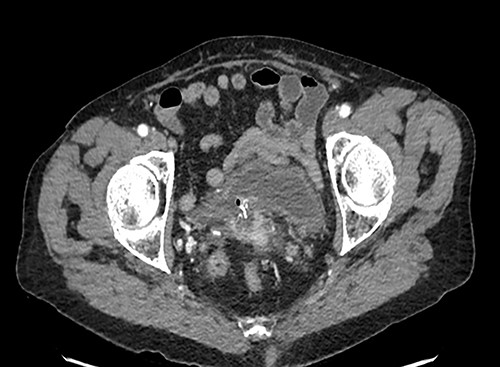

A 90-year-old woman presented with abdominal pain and pneumaturia; in her medical history we find a laparotomy mesh rectopexy 15 years ago. CT scan showed inflammation around the mesh that can also be seen entering the bladder (Figs 5 and 6).